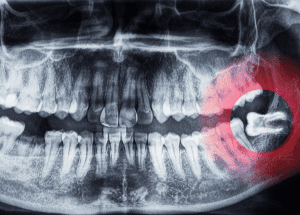

Procedimento que remove a polpa infectada preservando o dente natural. Realizado com instrumentos automatizados, Ozonioterapia e Terapia fotodinâmica para máxima precisão.

Salve seu dente com Tecnologia

Procedimento que remove a polpa infectada preservando o dente natural. Realizado com instrumentos automatizados, Ozonioterapia e Terapia fotodinâmica para máxima precisão.

Salve seu dente com Tecnologia